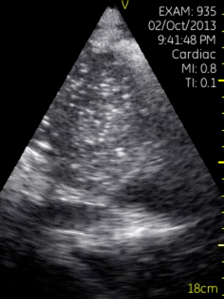

62 year old with weight loss, tachycardia and progressive dyspnea…what do you see?

scroll below!

This was a case of pre-tamponade/tamponade.  Here is a view a few minutes later, with the guidewire in. This was a case of malignant pericardial effusion.